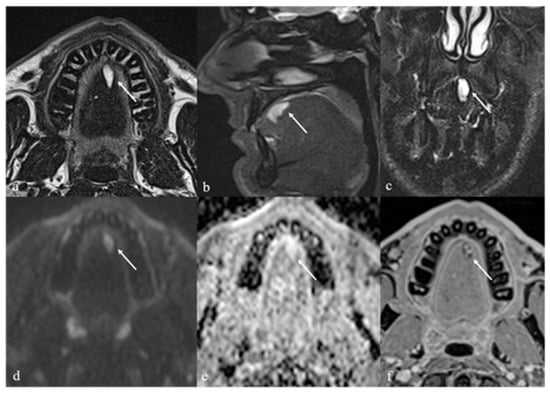

5.1. Venous Malformations

| Venous malformation [1,9] | CT: phleboliths MRI: high T2 SI, +CE | Other vascular malformations, schwannoma, dermoid cysts |